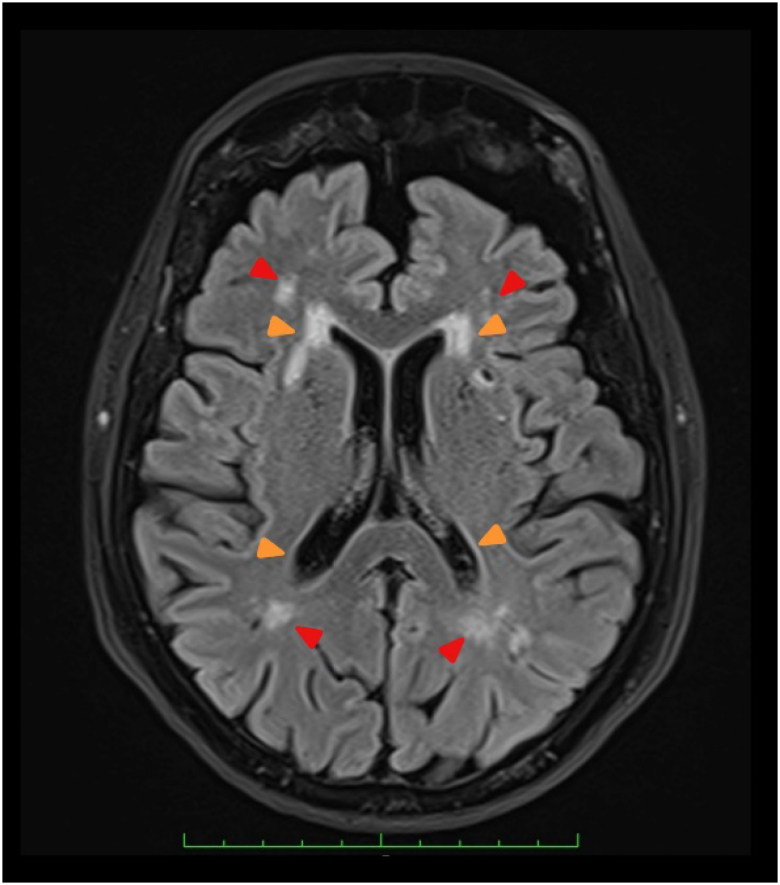

血管性认知障碍(VCI)是仅次于阿尔茨海默病的第二大认知障碍病因。血管性认知障碍包括因血管病变(如大面积梗塞或出血、微梗塞、微出血、腔隙性梗塞、白质高密度和血管周围空间扩张)导致的认知能力下降。病理生理机制包括直接组织损伤、小血管疾病、炎症(炎症+老化)、萎缩和神经传递改变。VCI 的诊断采用不同的临床和放射学标准。它可能导致长期残疾和生活质量下降。降低认知障碍发病率的一个重要因素是通过控制传统和非传统的脑血管风险因素来预防中风。本文回顾了脑卒中认知障碍的范围、流行病学、风险因素、病理生理学、诊断、现有治疗和预防策略。

Vascular cognitive impairment (VCI) is the second most common cause of cognitive impairment after Alzheimer's disease. The VCI spectrum involves a decline in cognition attributable to vascular pathologies (e.g., large infarcts or hemorrhages, microinfarcts, microbleeds, lacunar infarcts, white matter hyperintensities, and perivascular space dilation). Pathophysiological mechanisms include direct tissue injury, small vessel disease, inflammaging (inflammation + aging), atrophy, and altered neurotransmission. VCI is diagnosed using distinct clinical and radiological criteria. It may lead to long-term disability and reduced quality of life. An essential factor for reducing cognitive impairment incidence is preventing stroke by managing traditional and non-traditional cerebrovascular risk factors. This article reviews the spectrum of VCI, epidemiology, risk factors, pathophysiology, diagnosis, available treatment, and preventive strategies.